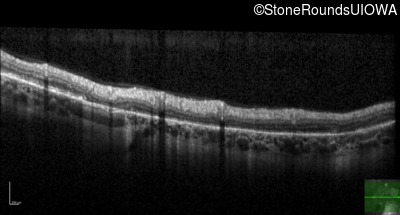

Optical Coherence Tomography - Left - 20/60 +2 sc

Exemplar / OCT Stack